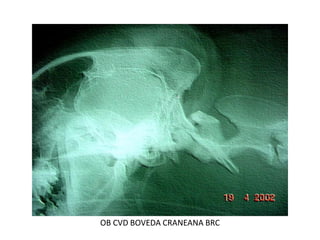

OB CVD BOVEDA CRANEANA BRC

OB CVD Fractura bóveda craneana

OB CVD 16 DISPLASIA OCCIPITAL

DX> Hidrocefalia

Canino de 1 año de edad,

raza chihuahua con un área

radiopaca y un

abombamiento y presencia

de liquido en la parte

superior del cráneo . Se

nota la apariciencia

homogénea causada por la

perdida de curvas y partes

redondeadas normales de

el cerebro.

Vista lateral

rx craneo hidrocefalia